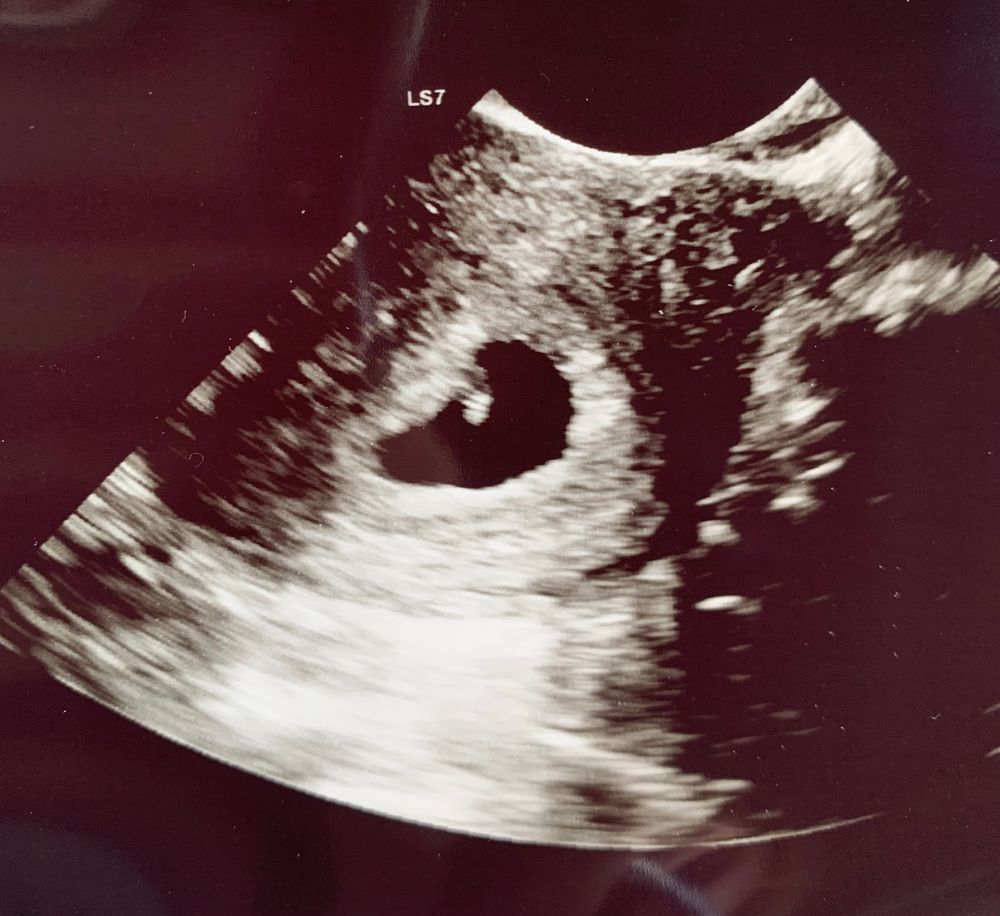

Вот и увидела я нашу горошинку

6 недель и 5 дней

сердечко уже во всю бьется❤️